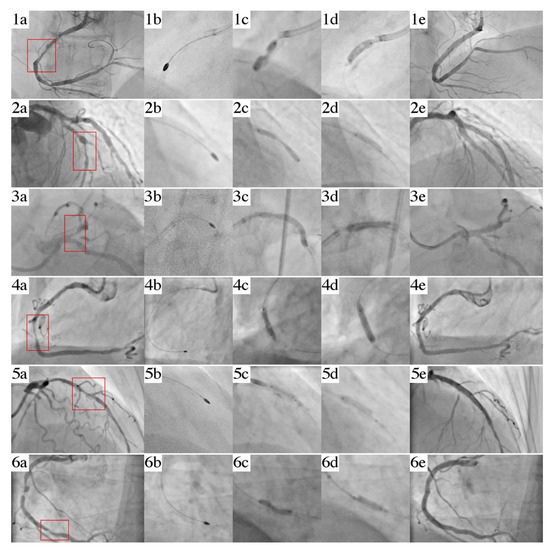

3. Cases

3.1. Case 1

3.2. Case 2

3.3. Case 3

3.4. Case 4

3.5. Case 5

3.6. Case 6